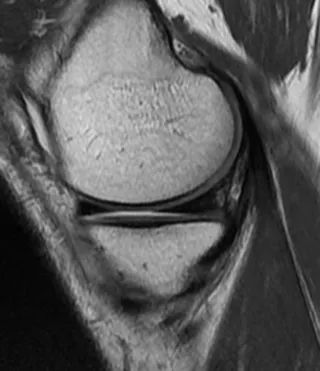

Sur les clichés sagittal et frontal, le ménisque normal est triangulaire en hypointense.Sur l'image sagittale la plus latérale, le ménisque est une structure en 'nœud papillon' constituée d'une section médio-sagittale associée aux cornes antérieure et postérieure (Figure 1).

Figure 1 Aspect IRM normal du ménisque médial.Coupe sagittale pondérée en densité de protons : Les angles méniscaux antérieur et postérieur sont des triangles hypointenses homogènes.Le ménisque est en forme d'arc et se compose de sections de la section médiane qui relient ses cornes antérieures devant lui et ses cornes postérieures derrière lui.